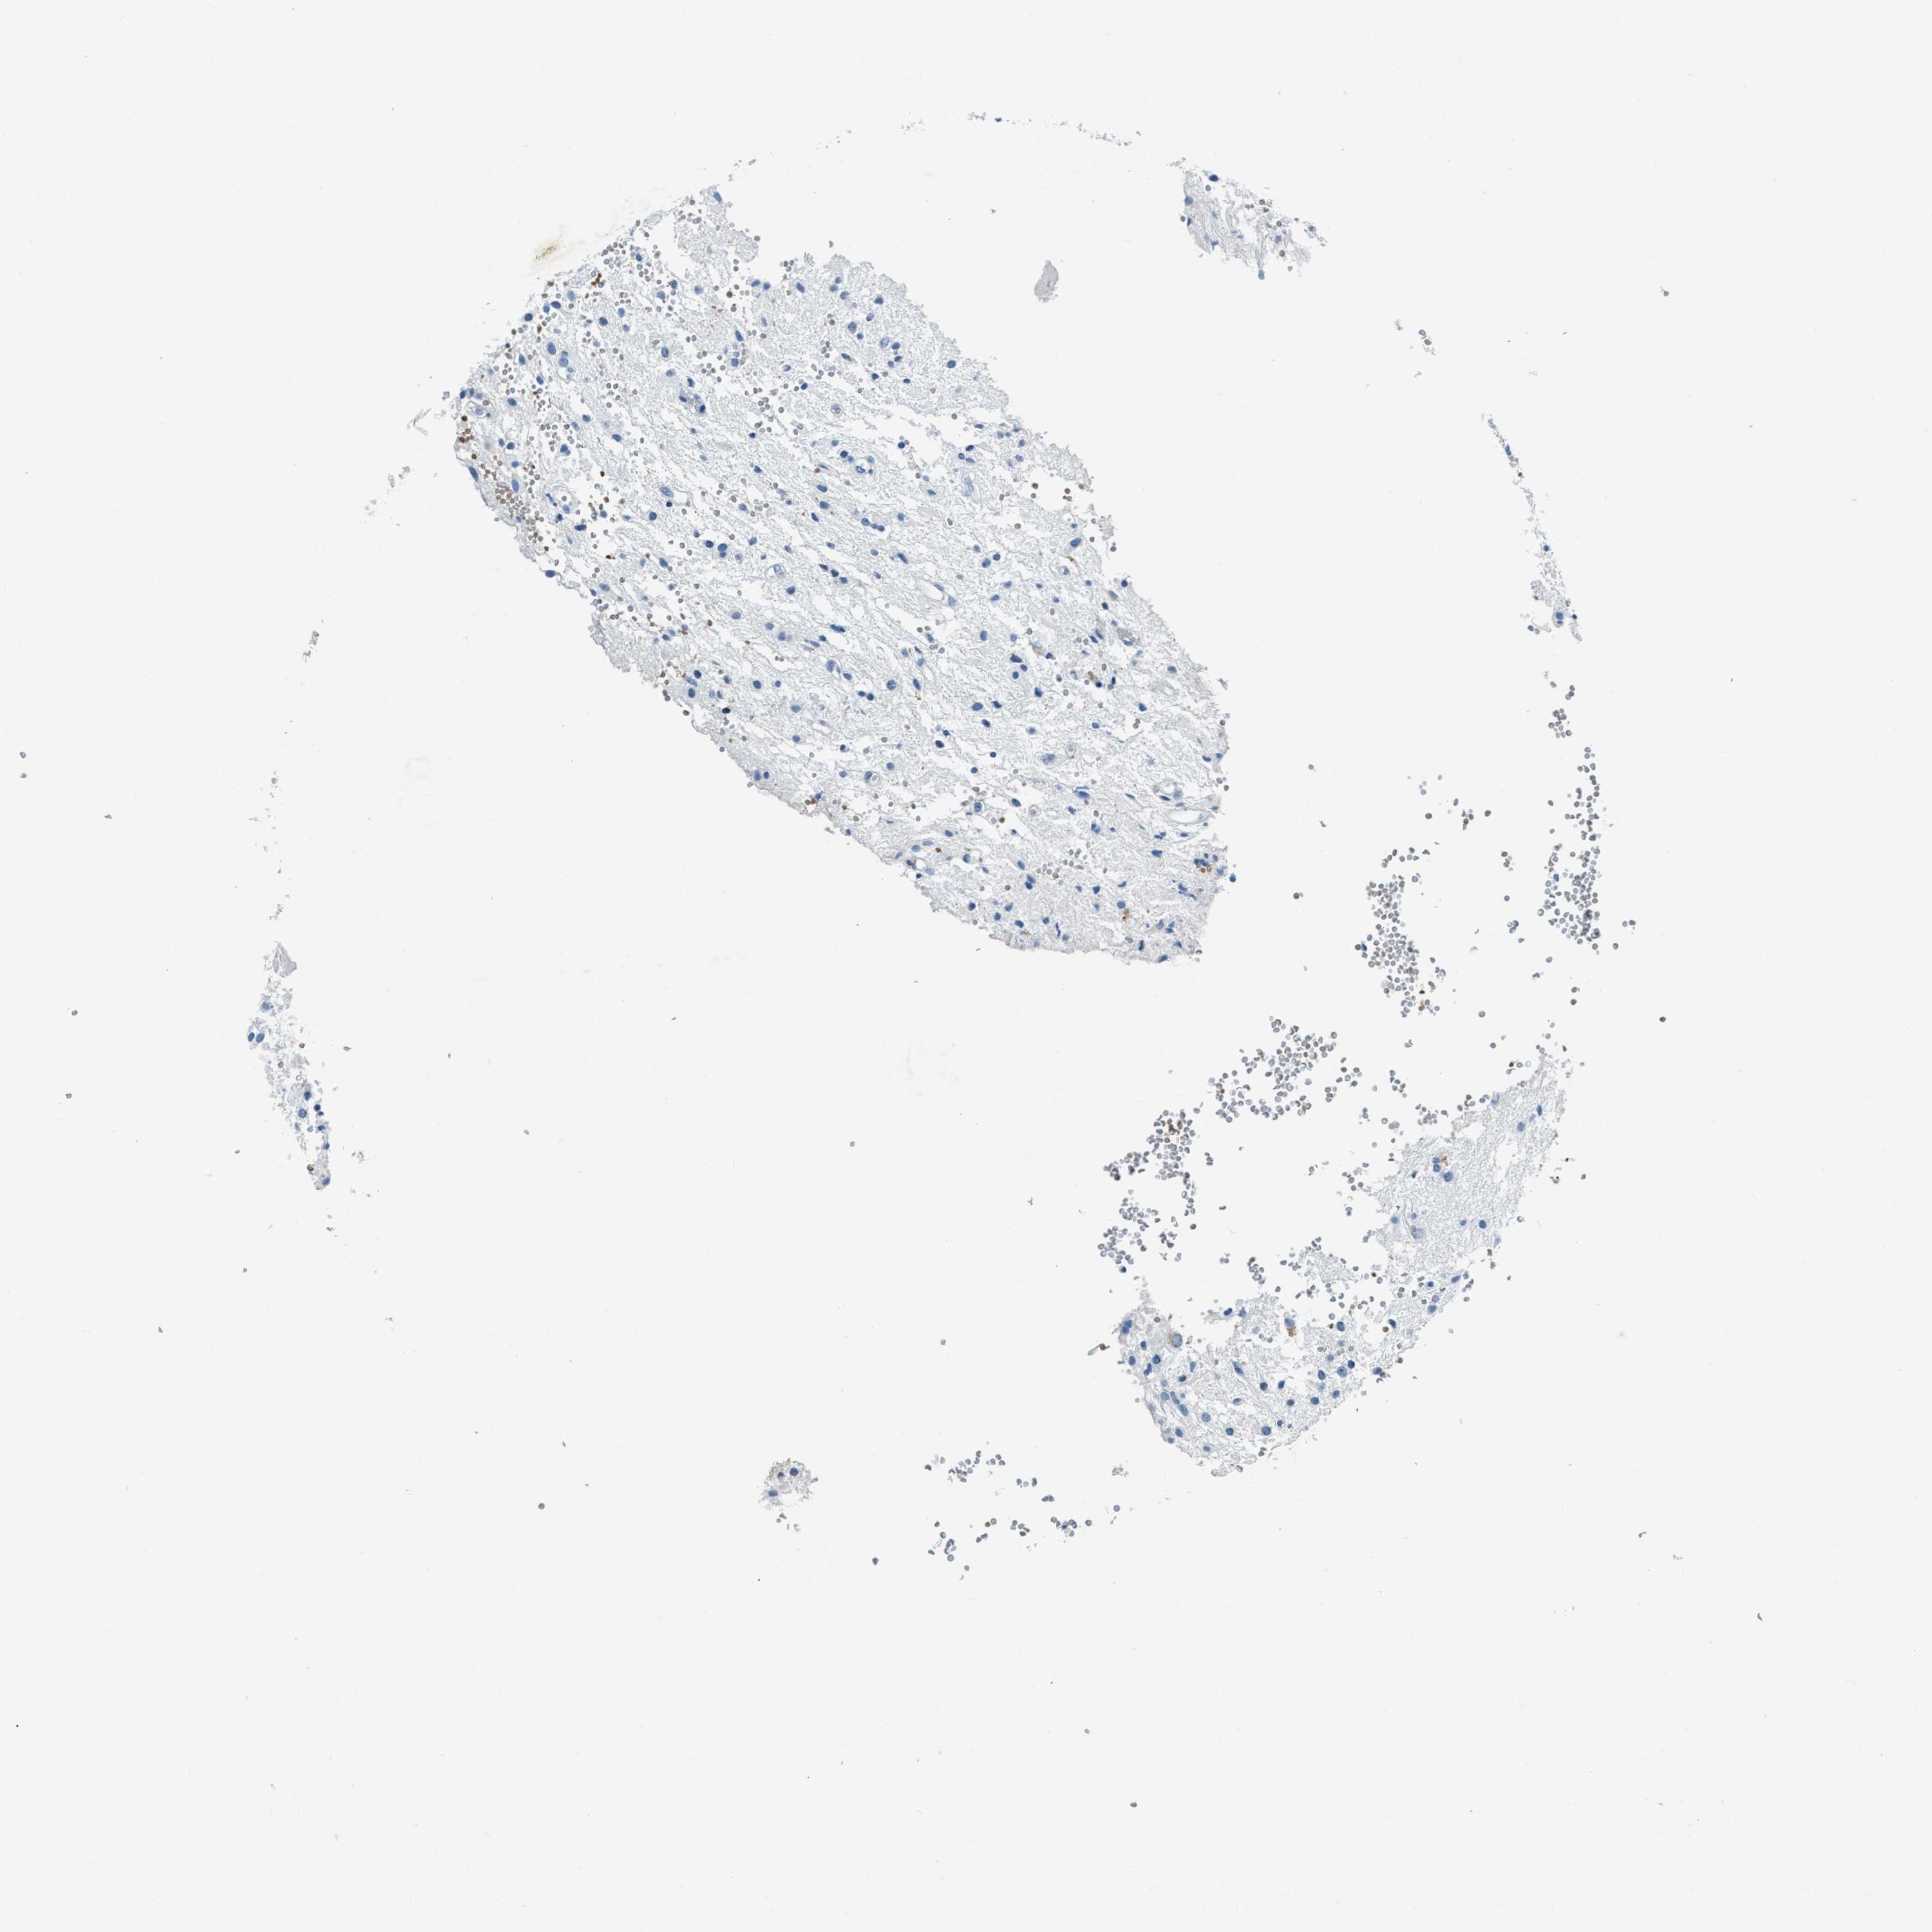

GLIOMA - Protein expressioni

A mouse-over function shows sample information and annotation data. Click on an image to view it in a full screen mode. Samples can be filtered based on level of antibody staining by selecting one or several of the following categories: high, medium, low and not detected. The assay and annotation is described here.

Note that samples used for immunohistochemistry by the Human Protein Atlas do not correspond to samples in the TCGA dataset.

Antibody stainingi

Antibody staining in the annotated cell types in the current human tissue is reported as not detected, low, medium, or high, based on conventional immunohistochemistry profiling in selected tissues. This score is based on the combination of the staining intensity and fraction of stained cells.

Each image is clickable and will lead to virtual microscopy that enables deeper exploration of all samples and also displays staining intensity scores, fraction scores and subcellular localization as well as patient and tissue information for each sample.

Antibody HPA016747

Antibody HPA026832

Staining

High

Medium

Low

Not detected

Intensity

Strong

Moderate

Weak

Negative

Quantity

>75%

75%-25%

<25%

None

Location

Nuclear

Cytoplasmic/membranous

Cytoplasmic/membranous,nuclear

Glioma, malignant, High grade

Glioma, malignant, Low grade